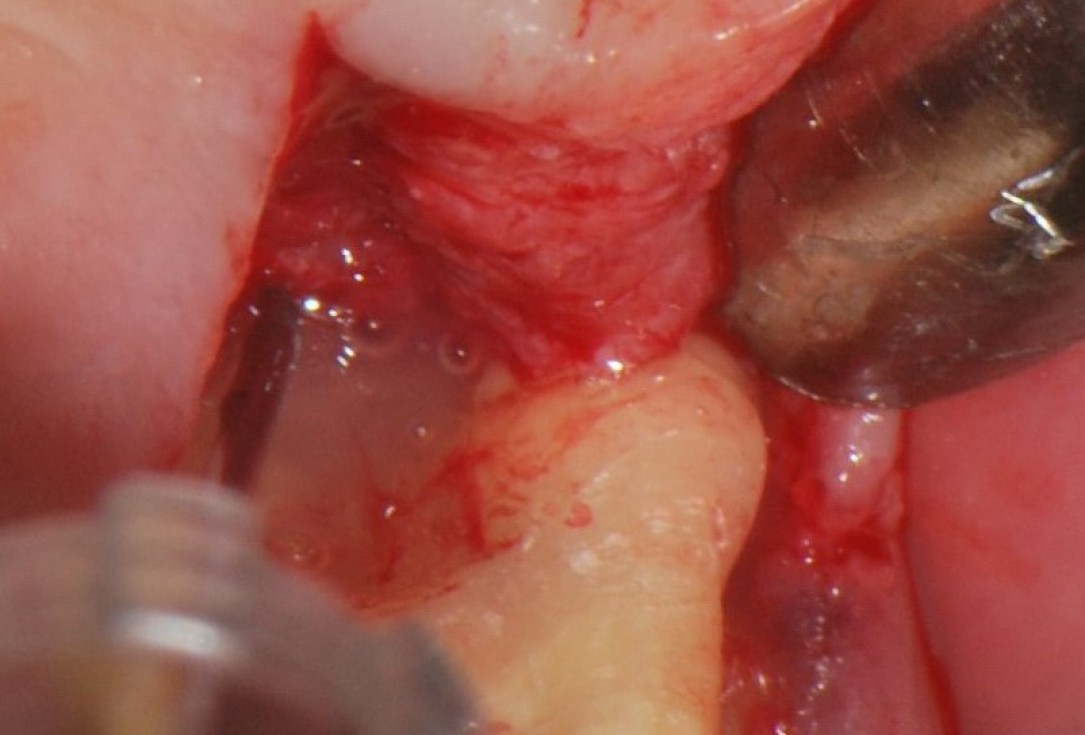

03/06 - Pre-surgical probing to determine furcation involvement.Treatment of a periodontal bone defect adjacent to an edentulous site using Straumann® Emdogain® - Prof. Dr. P. Windisch

04/06 - Flap elevation by a midcrestal incision and application of Straumann® Emdogain® to the defect site.Treatment of a periodontal bone defect adjacent to an edentulous site using Straumann® Emdogain® - Prof. Dr. P. Windisch